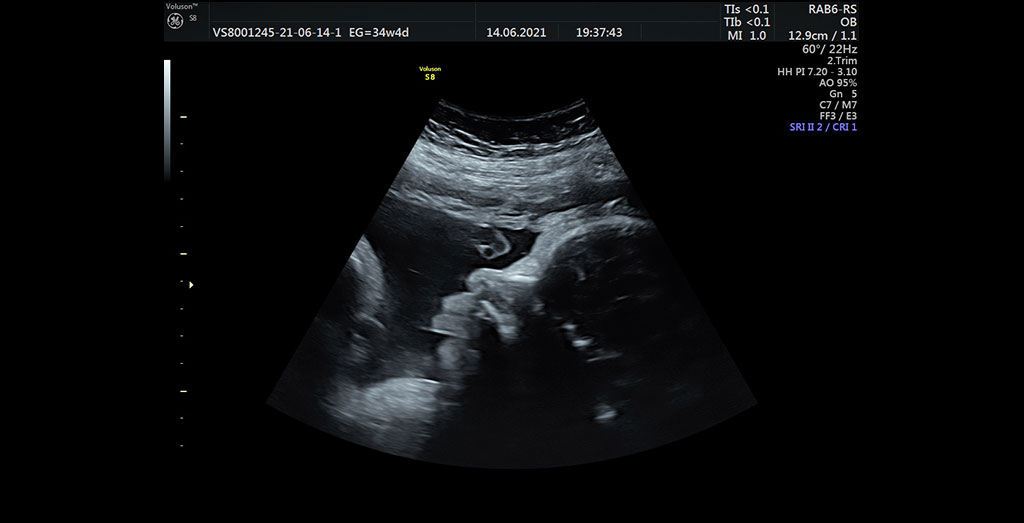

Ecografía Obstétrica

La ecografía obstétrica es una evaluación médica del embarazo mediante técnicas de ultrasonido en 2 dimensiones (2D) que permite el estudio del bienestar fetal. Además, la ginecóloga con este tipo de ecografías podrá valorar la anatomía del bebé, el crecimiento y los movimientos fetales, el cálculo del peso fetal estimado (PFE), la valoración de la cantidad del liquido amniótico y podrá realizar un examen de la morfología e inserción de la placenta.